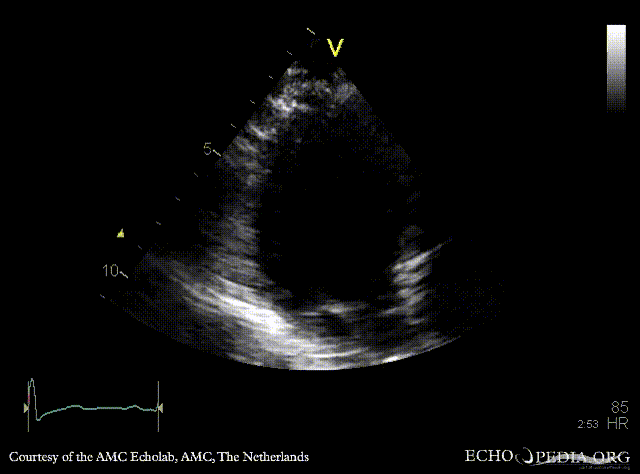

Subvalvular membrane

PSAX: subvalvular membrane PSAX: subvalvular membrane, zoom